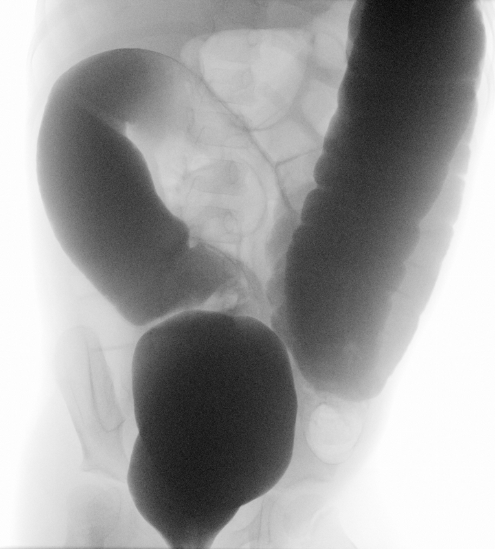

Sollte Ihr Kind direkt nach der Geburt Auffälligkeiten zeigen, werden wir zur Mitbeurteilung auf die Entbindungsstation oder auf die Neugeborenenstation hinzugezogen. Sollten sich erst zu einem späteren Zeitpunkt Symptome zeigen, die an einen Morbus Hirschsprung denken lassen, erfolgt meist eine Vorstellung in unserer kinderchirurgischen Sprechstunde. Wir bitten Sie zu diesem Termin bereits vorhandene Untersuchungsergebnisse (z.B. Ultraschall, Laborwerte, Ergebnisse aus anderen Krankenhäusern) mitzubringen. Wir werden dann entscheiden, welche weiteren Untersuchungen notwendig sind. Diese können eine Ultraschalluntersuchung des Bauches, eine Röntgen-Untersuchung des Dickdarms („Colon-Kontrast-Einlauf“) oder eine Gewebeentnahme aus der Schleimhaut des Dickdarms zur mikroskopischen Untersuchung beinhalten. Letztere ist der Goldstandard zur Diagnosesicherung eines Morbus Hirschsprung.

Bestätigt sich in den Untersuchungen die Diagnose eines Morbus Hirschsprung ist in der Regel eine Operation notwendig, um den Darmabschnitt mit den fehlenden Nervenzellen zu entfernen. In Ausnahmefällen ist der betroffene Darmabschnitt aber sehr kurz (sog. „ultra-short-Variante“), in diesen Fällen gibt es verschiedene Behandlungsmethoden, die ausführlich mit Ihnen besprochen werden können. Insbesondere bieten wir die Option der Sakraler Neuromodulation im Rahmen von klinischen Studien an, mit der wir sehr gute Therapierfolge bei betroffenen Patienten erzielen.

Bei früher Diagnosestellung und langstreckigen Segmenten wird oft zunächst ein künstlicher Darmausgang angelegt, um den betroffenen Darm auszuschalten und das Kind gedeihen zu lassen. Für die definitive Operation zur Entfernung des betroffenen Abschnitts sind verschiedene Techniken beschrieben: entweder erfolgt die Entfernung vom Anus aus oder per Bauchspiegelung (minimal-invasiv, laparoskopisch), manchmal auch in Kombinationstechnik. Die von uns angewandte Technik entspricht dem Operationsverfahren nach Swenson.